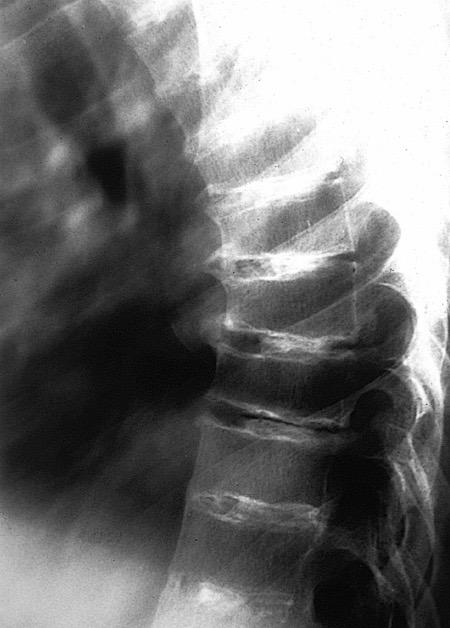

Fracturas dorsales

Wu M.-H., Huang T.-J., Cheng C.-C., Li Y.-Y., Hsu R.W.-W. Role of the supine lateral radiograph of the spine in vertebroplasty for osteoporotic vertebral compression fracture: A prospective study. BMC Musculoskelet. Disord. 2010;